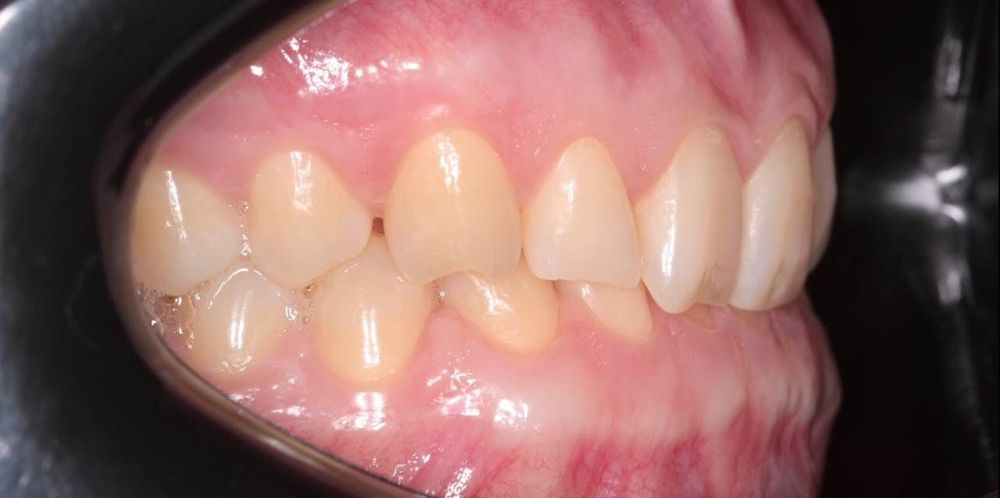

Пациент обратился с проблемой глубокого прикуса: верхние зубы сильно перекрывали нижние. Это не только портило улыбку, но и создавало дискомфорт при жевании, ускоряло стираемость эмали и нагружало височно-нижнечелюстной сустав.

- глубокий прикус исправлен

- восстановлено нормальное жевание и комфорт в суставе